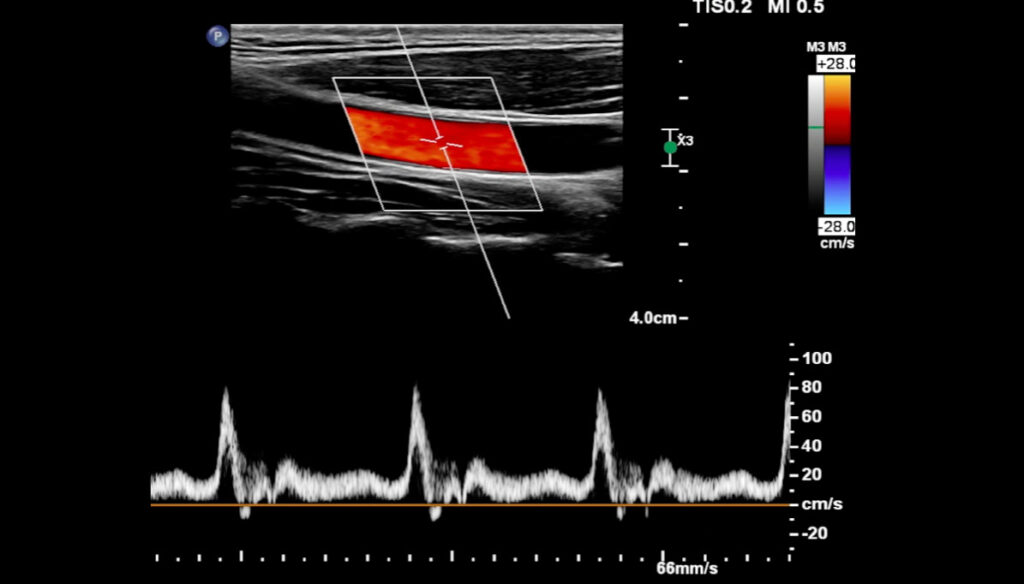

Eco-color-Doppler

Eco-color-Doppler, che cos’è? L’eco-color-Doppler (ECD) è una tecnica ecografica che sfrutta alcune proprietà fisiche degli ultrasuoni (in particolare il cosiddetto effetto Doppler) per studiare le